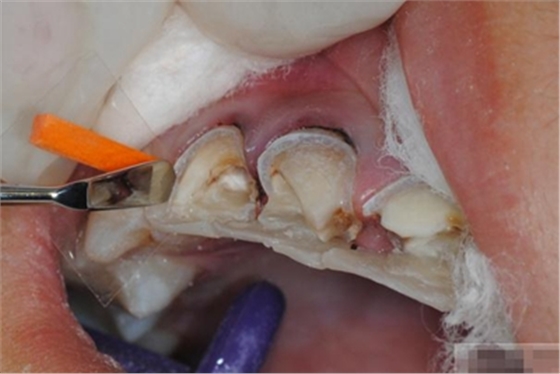

【檢查】12,11,21,22,均行玻璃離子充填,各牙不同程度部分充填物脫落,探(—),叩(—),冷刺激無(wú)反應(yīng),無(wú)松動(dòng),牙齦顏色粉紅,質(zhì)地堅(jiān)實(shí)而有彈性,點(diǎn)彩正常,牙結(jié)石(—);牙髓活力測(cè)試無(wú)反應(yīng)。

【診斷】12,11,21,22牙體缺損